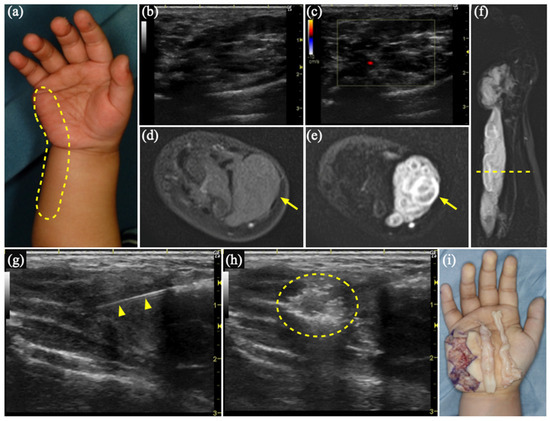

3.2. Case 1

| 1 | 2 | F | Rt hand, forearm | VM | US, MR | Sc, 4 times | Schwannoma | 1893 |